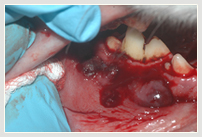

Neben der allgemeinen Untersuchung und der Untersuchung der Zahntaschen mittels Parodontalsonde sind ZAHNRÖNTGEN unumgänglich für eine komplette Diagnostik von Parodontalerkrankungen und bei Zahnresorptionen vor allem bei der Katze (FORL). Dabei werden spezielle Techniken mit Dentalfilmen wie beim Menschen verwendet.

In der Kleintier-Ordination Mittertreffling wird eine moderne digitale Entwicklung verwendet, die die Strahlenbelastung für Ihr Tier verringert. Ohne Zahnröntgen wird das Ausmaß des Knochenverlustes oft unterschätzt und bei der Katze viele Zahnresorptionen übersehen oder unterschätzt. Zudem ist bei einer wie in der Tier-Zahnheilkunde in einer Sitzung durchgeführten Wurzelbehandlung (Endodontie) eine Kontrolle durch Zahnröntgen unbedingt notwendig. Selbst Tumoren können sehr gut erkannt werden und auch die Kontrolle einer Zahnbewegung (Orthodontie) sollte durch Zahnröntgen erfolgen.

Eckzahn Fraktur Eckzahn mit Feile Eckzahn nach Wurzelbehandlung